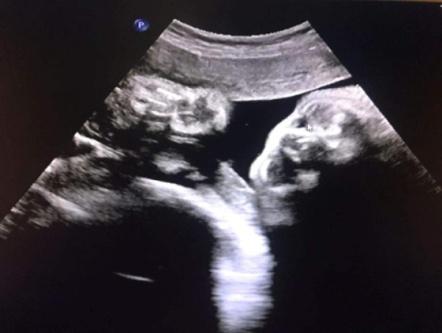

典型案例:孕妇,37岁,孕32周常规产检,系统检查胎儿及附属物,发现胎儿双侧眼眶内下方均可见一无回声区,大小分别约:右侧0.4x0.3cm、左侧0.8x0.7cm,边界清晰,内壁光滑,内透声好,左侧无回声内可见斑块状高回声,彩色多普勒检查其内未见血流信号,余未见异常;孕34周及36周随访复查,双侧无回声区消失。

超声动态观察,能在孕期显示并诊断胎儿鼻泪管囊肿,动态监测其转归,减少孕妇的焦虑,避免不必要的引产。